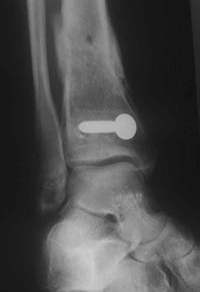

1 Jahr nach der Operation

Der Patient lief schmerzfrei!